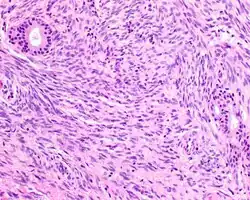

| A high-power view of a hematoxylin- and eosin-stained slide showing respiratory epithelial inclusions within a spindled cell neoplasm showing characteristics of a biphenotypic sinonasal sarcoma | |

- Infiltrative, highly cellular spindled cell neoplasm is poorly circumscribed and unencapsulated. Bone destruction or invasion is common. The cells show medium to long fascicles (nerve fibers), with a herringbone pattern. The cells are remarkably uniform with elongated nuclei. Delicate strands of intercellular collagen without ropy or dense deposition are seen. A very characteristic concurrent surface-type respiratory epithelial proliferation is found from the surface or in small cystic spaces around the cancer cells, often forming glands. The background may have a rich vascularity and usually has a small number of scattered lymphocytes. Extra growths or mitoses are rare, while necrosis, ulceration, and hemorrhage are usually absent.